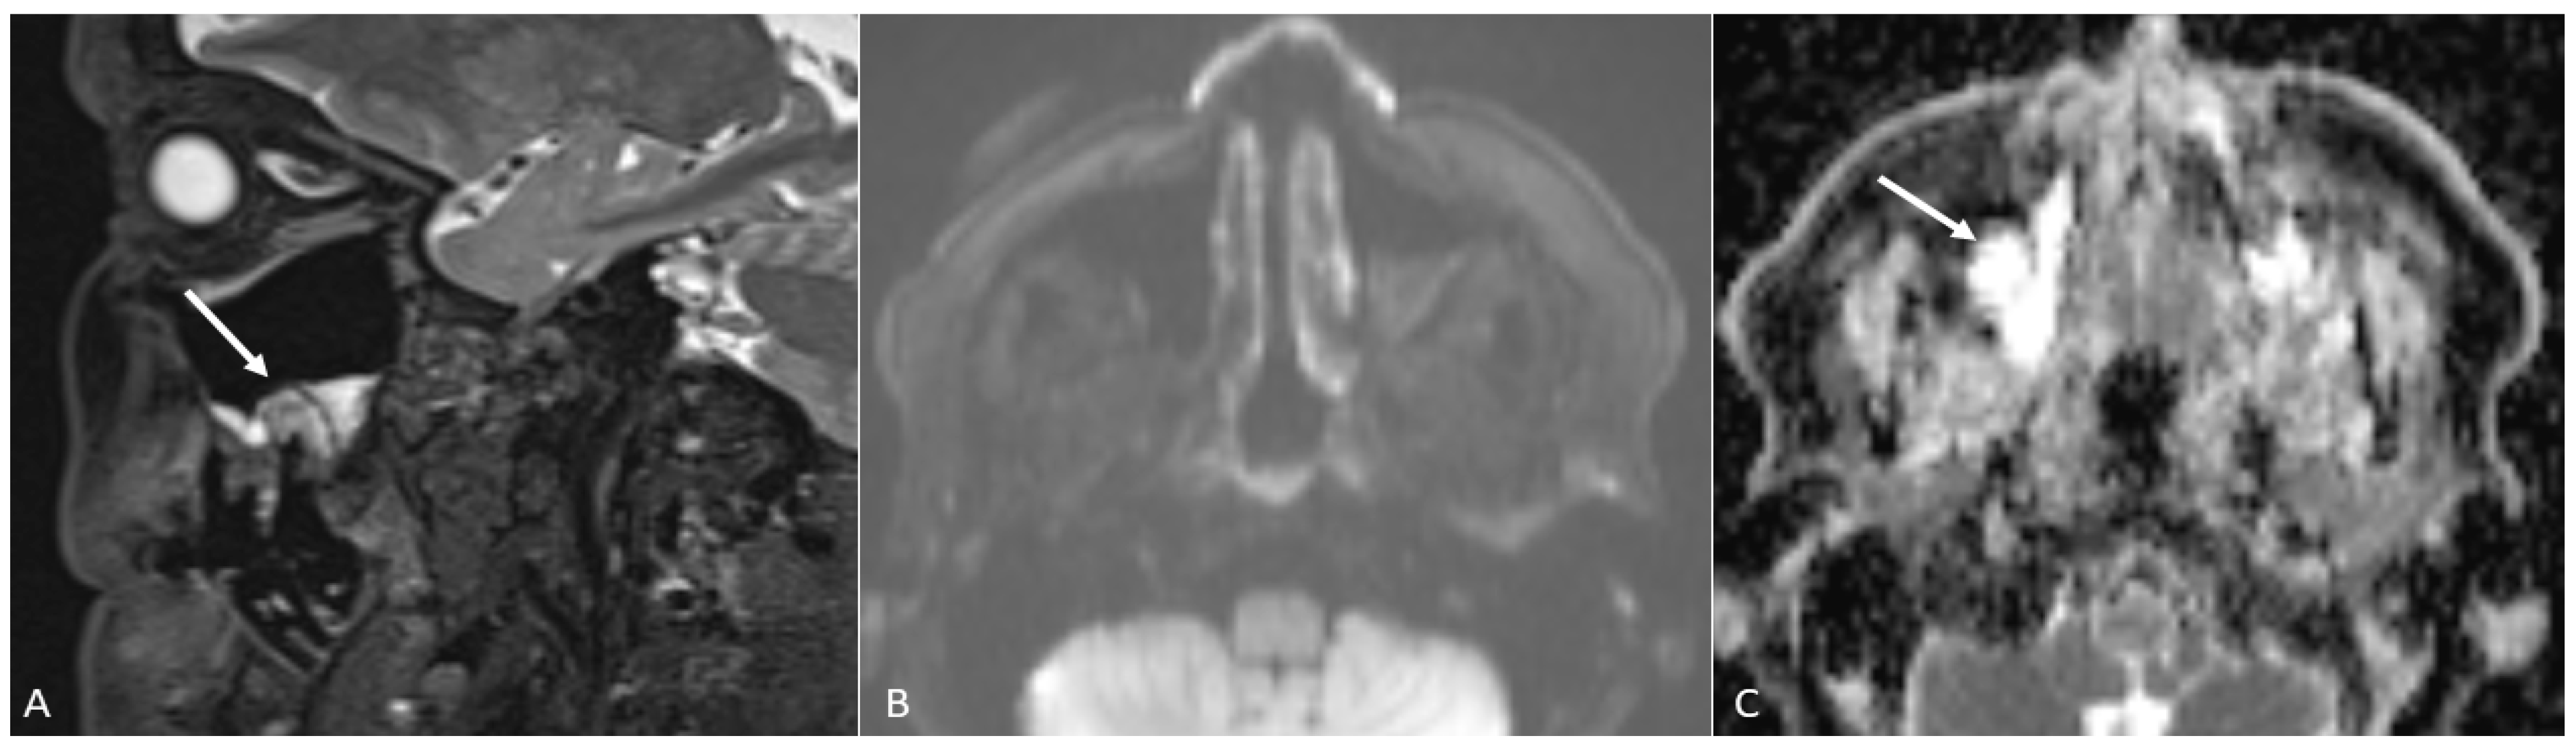

- Open mouth technique. Patients open their mouth and the acquisition is obtained with quiet respiration. A device (i.e., a 50 mL syringe) can be used between teeth to ensure the maintenance of the right position [28]. It allows the separation of the palatal mucosa from the muscular component of the tongue clarifying the exact origin, infiltration, and thickness of tumoural masses (Figure 12 and Figure 13).

- Water distension of the oral vestibule. This technique is exclusively used on MRI examinations since MRI has a high contrast for liquids by using specific sequences, especially T2 sequences. Water distension of the oral vestibule is performed by asking patients to drink 20–40 mL of still water and keep it in the mouth for the time necessary to acquire the images (T2 and pre- and post-contrast T1 sequences) [47]. This manoeuvre distends the oral vestibule and the presence of water provides excellent natural contrast between the lesion and the adjacent mucosal surfaces (Figure 17).